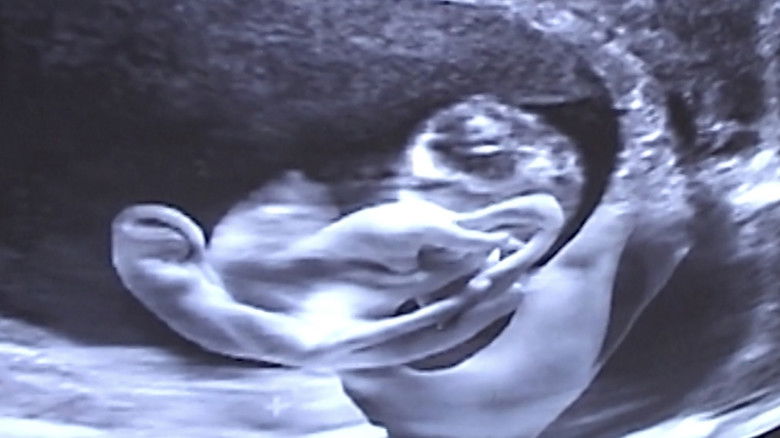

Кадры